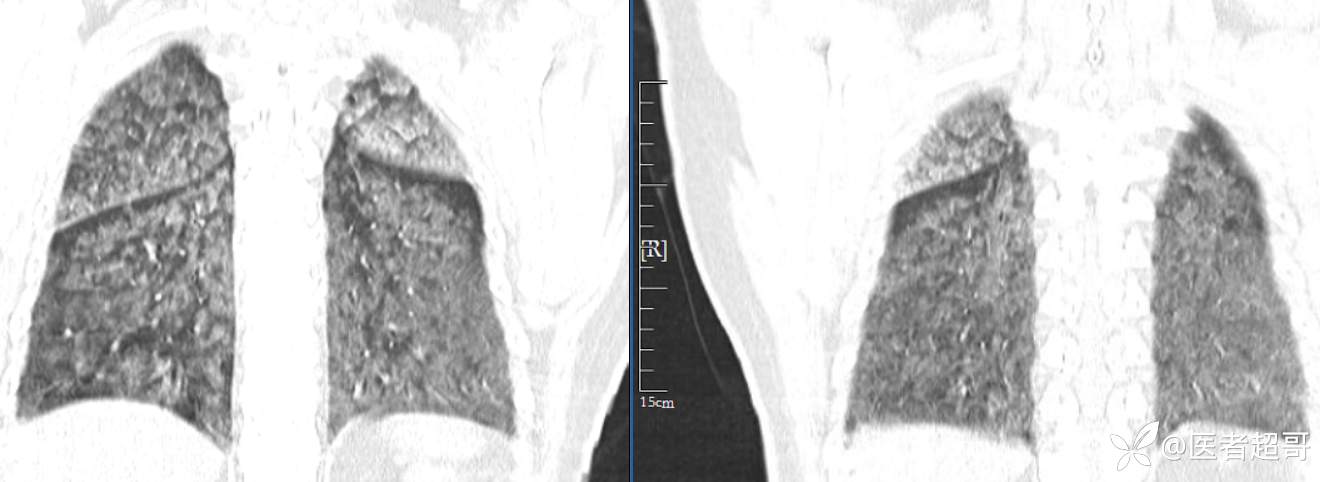

患者性别:女

患者年龄:47岁

主诉:胸痛就诊

简要病史:因“胸痛就诊”,行冠脉CTA检查,数小时后出现高热,伴畏寒寒战、气喘,暗红色泡沫样痰。

急性肺水肿 (17)